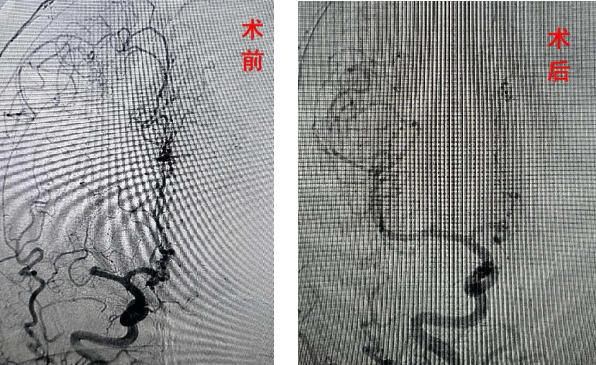

基于患者的临床表现和体检结果,考虑为脑血管意外。在120急救、急诊科和神经内科的联合协作下,迅速启动了脑卒中绿色通道。紧急进行头颅CT检查未发现脑出血征象,随后给予静脉溶栓治疗但患者症状缓解不明显,存在严重致残风险。经过全面分析,立即进行了急诊脑血管造影检查,结果显示患者右侧大脑中动脉闭塞。随即进行了取栓术,手术过程顺利。

术后患者恢复状况良好,目前已能下床活动。